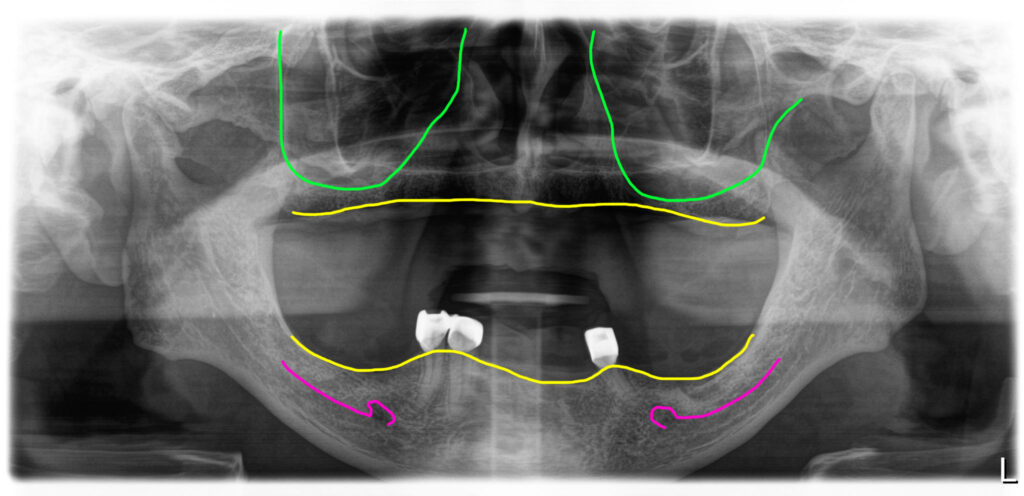

위아래 틀니를 오랫동안 사용하고 계셨던 70대 아버님이셨어요. 상악동부위에 뼈가 좀 부족했지만 뼈이식이 가능한 상태였습니다.

아래에는 부분틀니를 쓰고 계셨는데 남아있는 치아를 잘 관리하셔서 잇몸이 튼튼하고 위치도 좋았습니다. 그래서 아래 지대치로 사용중이었던 3개의 치아는 남기고 전체임플란트를 하기로 했습니다.